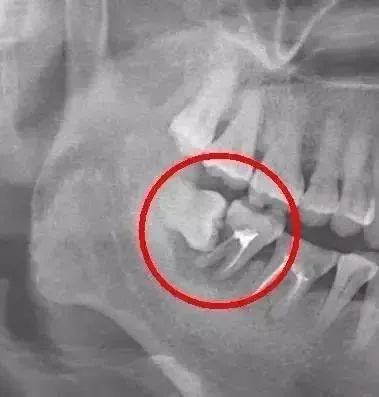

下图为来我院拔除的常见阻生智齿

病人为22岁的女性,现处于正畸治疗阶段。在感觉到左上牙咀嚼无力就及时来我院就诊。刘建华医生在x光片检查后发现,左上第三磨牙为低位阻生,压迫第二磨牙牙根,导致第二磨牙咀嚼无力,偶有酸软感。当时决定拔出。这位患者对拔牙有恐惧,拔牙前十分害怕,但是过程无痛,拔牙后表示非常轻松。